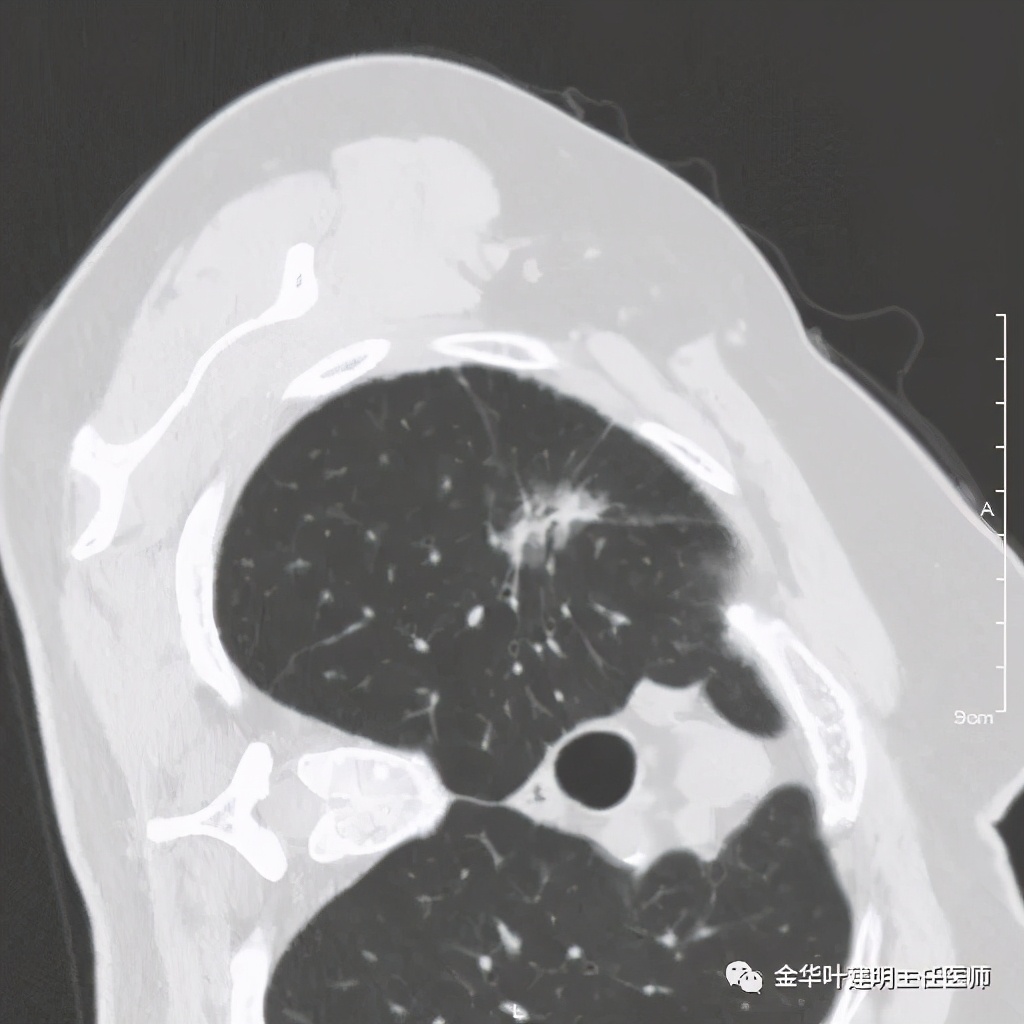

一、浸润性腺癌贴壁生长型:

影像特征:肺内 纯磨玻璃结节,几乎不见实性成分 ;瘤肺边界清楚,紫色箭头示局部有细毛刺征;绿色箭头示有血管进入病灶;总体密度较低,轮廓清楚。要注意的是:贴壁生长型肺浸润性腺癌可以在2-3厘米或以上,也可小到亚厘米程度,密度高低可以有所区别,有时与原位腺癌、微浸润性腺癌、不典型增生等在影像上有交叉,不能完全仅凭影像百分百区别。但总体上,恶性程度低,预后好。